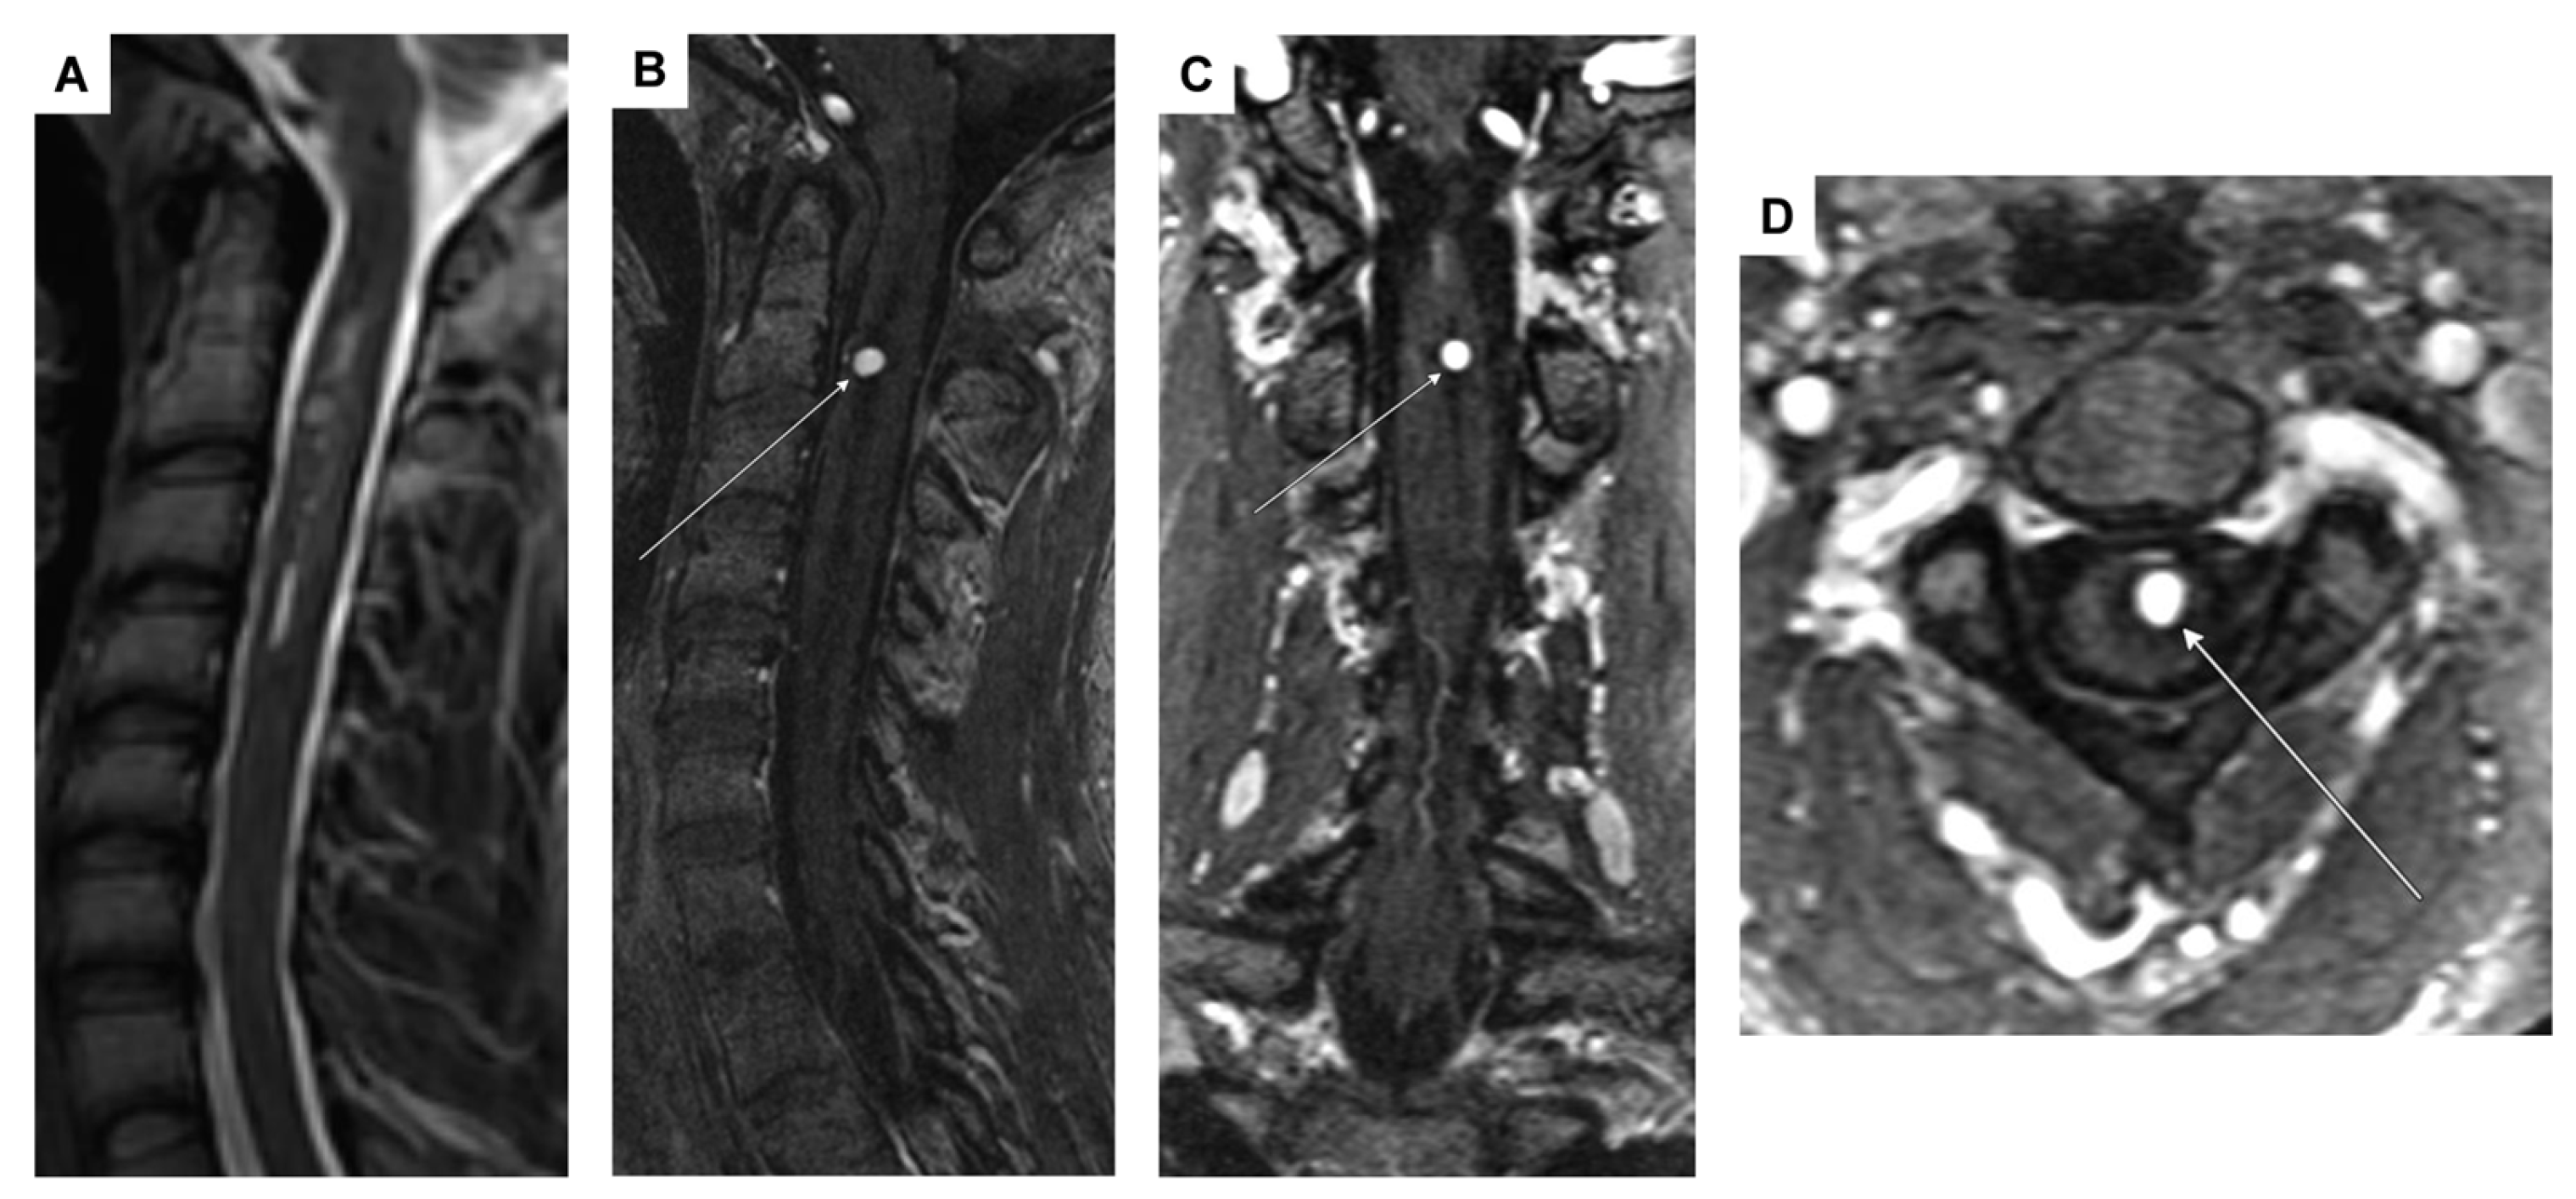

| 3 | F | 25 | acute headaches, complete tetraplegia, bradypnea, and asystole → cardiopulmonary resuscitation with ROSC | hypoesthesia on the left side at C6 and left thoracic and abdominal areas, left hemiparesis, tremor, and hemiataxia | spinal intramedullary aneurysm at C2 with perimedullary fistula | aneurysm | multiple DSA, multiple spinal MRI | surgical procedure (arterial feeder coagulation) |